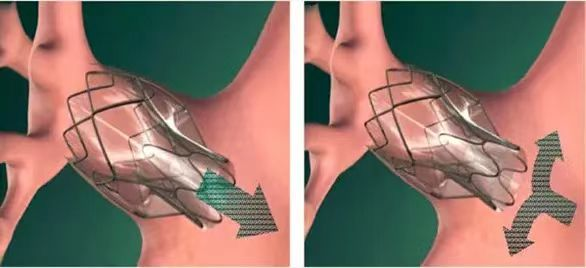

据悉,经支气管镜单向活瓣肺减容术,是一种支气管镜下介入治疗的新技术,放置在支气管内的活瓣,允许分泌物和气体从活瓣远端肺组织排出,但阻止气体进入活瓣远端肺组织,从而使靶肺组织逐渐萎陷不张,达到减容的目的。该新技术具有疗效显著、创伤小、病人耐受好、术后康复快、并发症少和住院时间短等优势。经支气管镜单向活瓣肺减容术的成功开展,为广大不均质肺气肿表型、叶间裂完整的慢性阻塞性肺疾病患者带来了新的选择。